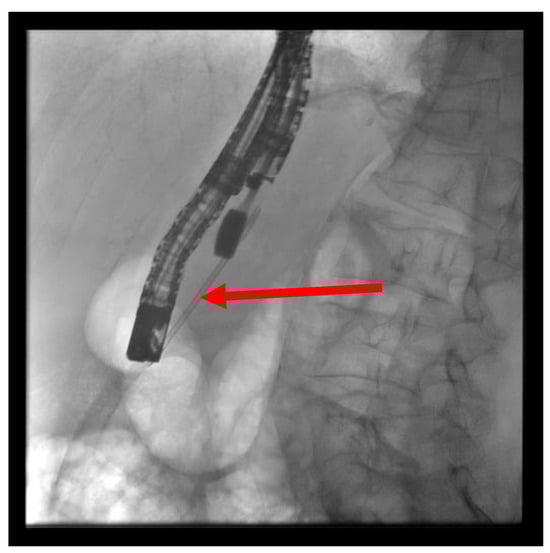

The patient is positioned prone on an X-ray fluoroscopy table and undergoes endoscopic ultrasound (EUS) using a therapeutic longitudinal scanner (e.g., EG 3270 UK, Hitachi Ultraschall, Berlin, Germany; GF-UCT 180, Olympus, Hamburg, Germany; Fuji EG-580UT2, Tokyo, Japan) following unsuccessful conventional ERP, with peri-interventional antibiotic administration i. v. (2 g ceftriaxone or 4 g tazobactam). Once the pancreatic duct is identified, a 19-G needle (Boston Scientific, Ratingen, Germany; Olympus, Hamburg, Germany) is used to puncture it in the direction of the anastomosis or papilla. Pancreatic juice is aspirated and sent for microbiological and cytological examination. Subsequently, the pancreatic duct is visualized via X-ray fluoroscopy following the instillation of the contrast medium (Figure 1 and Figure 2—selected from the clinical picture library of the reporting Dept. of Gastroenterology, Hepatology and General Internal Medicine as all the following figures).

Figure 2. Intraprocedural fluoroscopy (during EUS-guided procedure): Legend see also Figure 1.